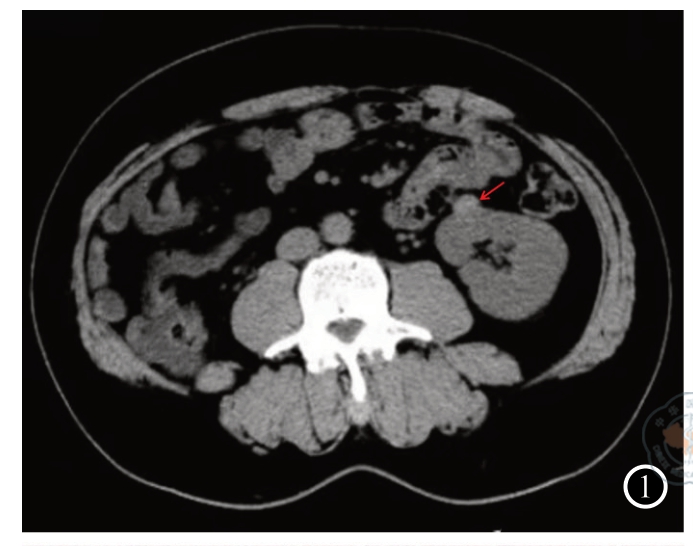

图4 肾炎性肌纤维母细胞瘤病理切片(HE ×10)

图7 肾炎性肌纤维母细胞瘤免疫组化(MSA×200) 注:图1中左肾下极可见一结节样密度增高影,凸向肾脏轮廓外,大小约 1.4 cm×1.1 cm(箭头所指)。图2可见左肾下极病变各期呈持续强化,边缘光滑(箭头所指)。图3可见肿瘤大小约为1.5 cm×1.1 cm×1.1 cm,切面灰白色,实性,质地中等。图4可见肾脏组织中见梭形细胞肿瘤,肿瘤细胞由纤维母细胞及肌纤维母细胞构成,细胞无明显异型性,呈束状、交织状排列,部分玻璃样变,淋巴细胞、浆细胞及组织细胞灶状聚集。图5可见肾炎性肌纤维母细胞瘤肿瘤细胞SMA呈阳性表达。图6可见肾炎性肌纤维母细胞瘤肿瘤细胞Desmin呈阳性表达。图7可见肾炎性肌纤维母细胞瘤肿瘤细胞MSA呈阳性表达